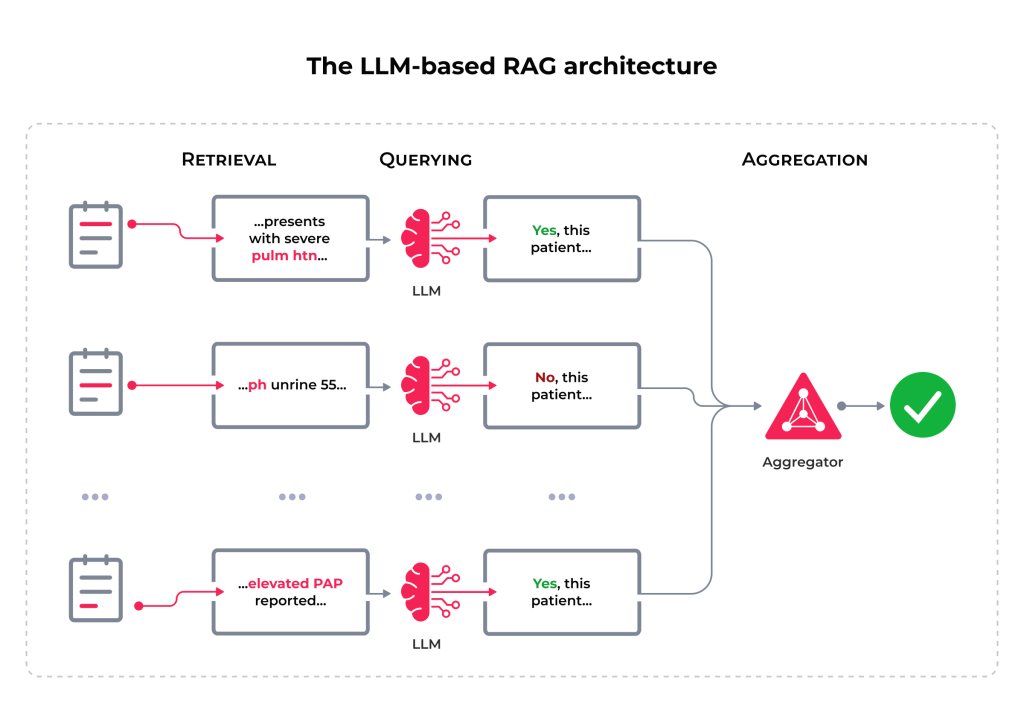

Combined with GenAI, RAG architecture offers you a unique opportunity to optimize these processes. It also excels in streamlining subject screening for clinical trials. Screening participants is typically a time-consuming and error-prone task, familiar to almost every clinical trial. However, the introduction of LLMs and Natural Language Processing (NLP) brings advanced solutions to increasing the efficiency of clinical research.

For instance, ChatGPT-4 can enhance clinical trial screening by using language capabilities to access external data, such as clinical notes. By incorporating RAG architecture, you can pull clinical notes as an external data source to capture the most relevant contexts. The workflow features four major steps: data loading, data splitting, vector embedding creation, and question answering. So, GPT combined with RAG reduces the time and cost of clinical trial recruitment.

However, some challenges exist, particularly in ensuring GPT’s ability to process clinical data to generate accurate results. A great solution is employing cost-efficient strategies like metadata filtering to focus on specific clinical notes and improve search precision. Tools like LangChain and LlamIndex strengthen the effectiveness of health systems by providing a structured way to store and retrieve data, reducing computational costs and time.